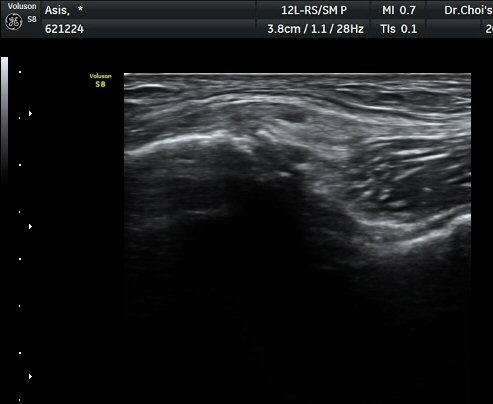

°üÂûµÇ°í(±×¸² 1) ¿ÜÃø´ëÅð±ÙÇǽŰæÀÇ ºÎÁ¾ÀÌ °üÂûµÊ(±×¸² 2, 3). Àü»óÀå°ñ±Ø Ⱦ´Ü¸é°Ë»ç¿¡¼­

°ß¿­°ñÀýµÈ °ñÆí°ú ¿ÜÃø´ëÅð±ÙÇÇ½Å°æ ºÎÁ¾ÀÌ °üÂûµÊ(±×¸² 4).